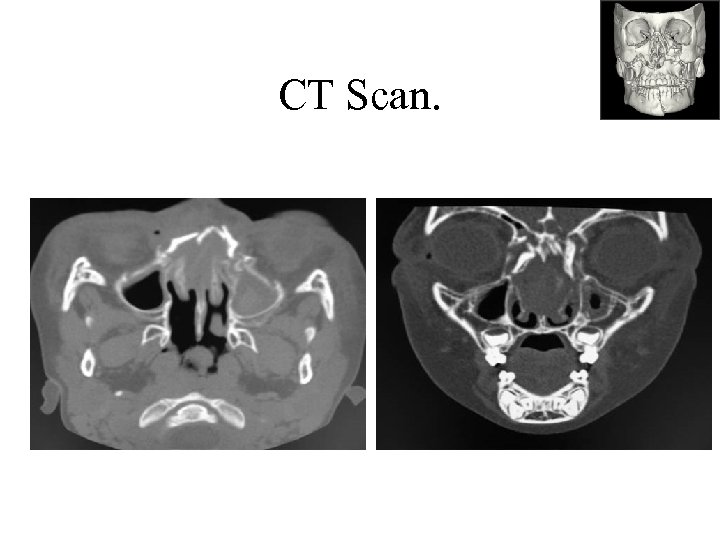

CT Scan.